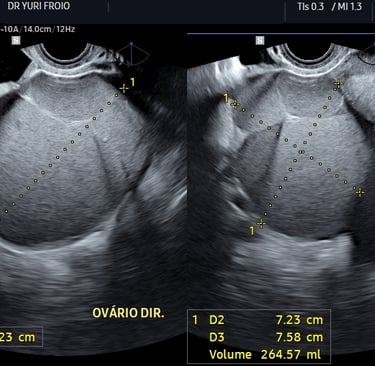

Ovários e útero: identificação de cistos endometrióticos e alterações morfológicas.